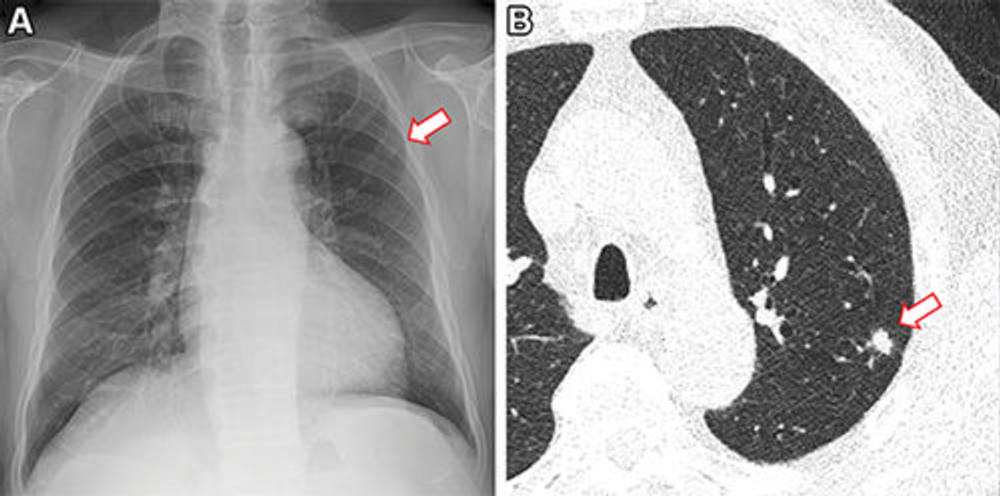

Figure 1. Frontal chest X-ray shows a subtle nodular opacity (arrow) in the right middle lung zone. Axial, non-contrast, low-dose chest CT scan shows a 1.1-cm solid nodule (arrow) in the right lower lobe.